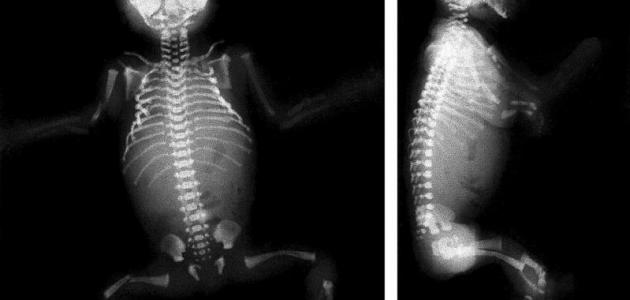

يتم الكشف عن هذه الحالة عن طريق إجراء أشعة سينية أو بالأشعة الفوق صوتية لمنظقة الحوض للطفل ابتداءاً من الشهر الثالث من عمره، ولا يجب أن تزيد هذه الفترة عن الشهر الرابع بأي حالٍ من الأحوال، فكلما كان الكشف مبكراً على هذه الحالة؛ كلما كان علاجها أسهل؛ ويكون الوقت الذي تستغرقه عملية العلاج أقل والشفاء أسرع.